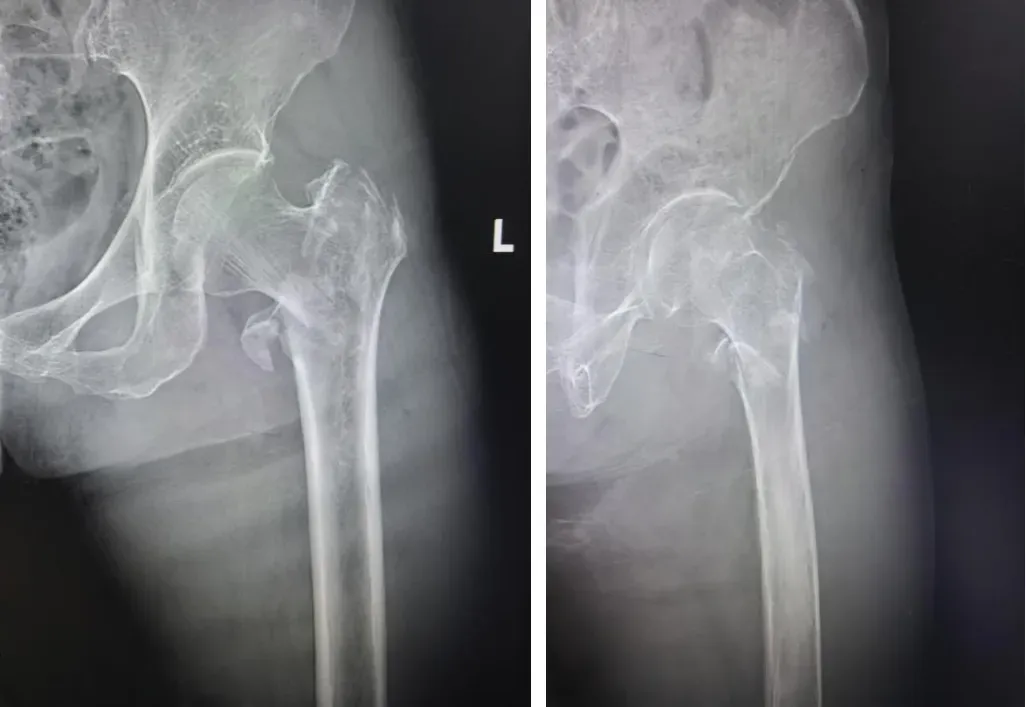

老人被紧急送医后,延安市中医医院第一时间开启高龄骨折绿色通道,加急完成心脏、肺部、凝血功能等检查。然而,检查结果却远超预期——左股骨粗隆间粉碎性骨折、入院时双下肢静脉血栓形成、多种基础病交织,让治疗难度陡增。看着卧床不起、痛苦呻吟的老人,家属满心焦灼:“年纪这么大,还带着血栓,这手术还能做吗?”

危急时刻,运动医学科在北京大学第三医院驻延专家陈有荣及科室主任庞军的带领下,紧急组织病情研讨。经过反复评估、缜密论证,在充分征得家属同意后,团队最终决定为患者实施微创PFNA内固定术。同时针对老人体弱、贫血、合并血栓等问题,团队同步采取纠正贫血、抗感染、抗血栓等对症措施;麻醉科精准调控患者血压、血糖至手术安全范围。